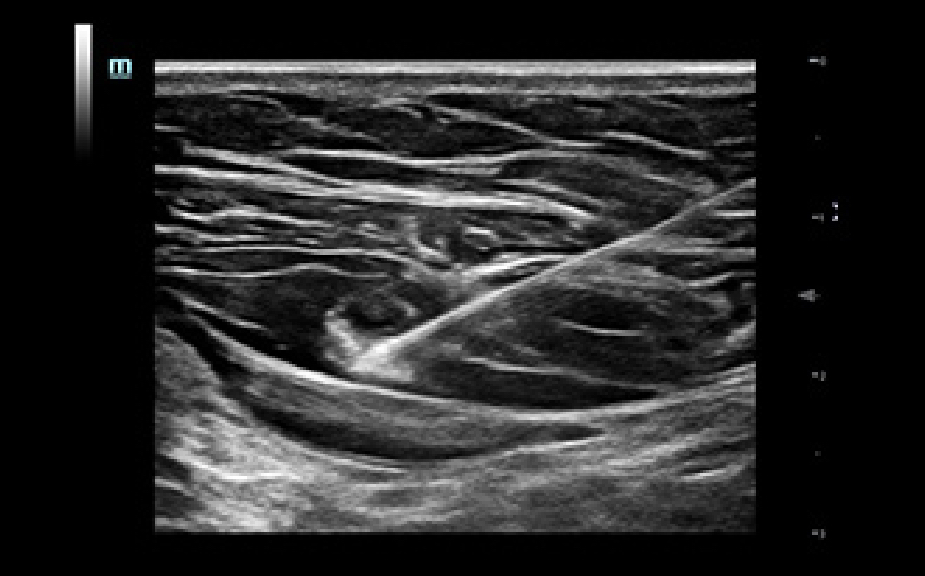

Solution de ponction par un seul op├®rateur